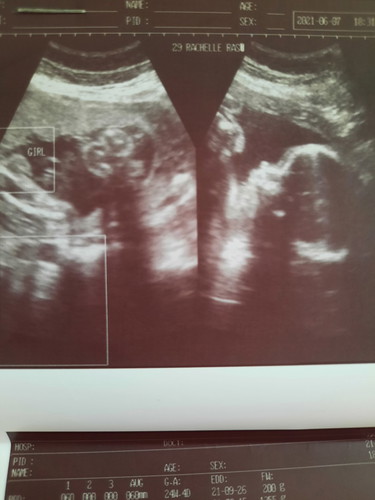

How accurate is the pelvic ultrasound at 25weeks?

Excited Momsh here😁😁😁🥰❤Possible pa ba mabago? Although it seems like sure n sure si Dra..eeee but still happy kung ano man gender ng palangga namin God's perfect gift❤❤ #firstbaby #1stimemom #pregnancy